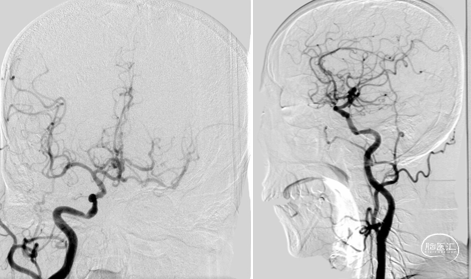

抽吸再通后造影,近端残余明显狭窄且局部毛糙,拟支架成型。

3.0*8 mm球扩支架,小压力,减少穿支损伤。

支架后造影

最后造影